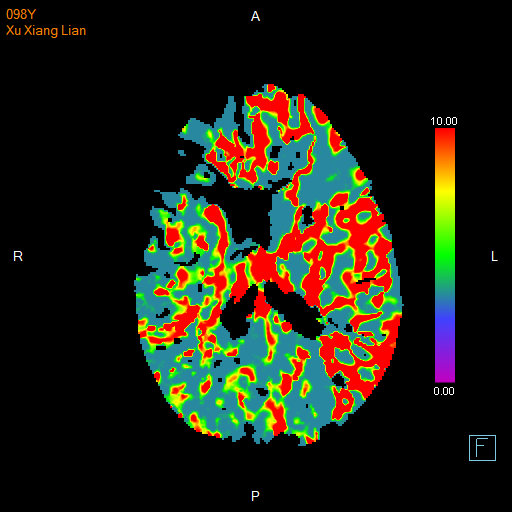

进一步的血管检查(CTA+CTP)发现了更严重的问题:王奶奶的左侧颈内动脉完全闭塞——这是脑梗中最凶险的类型之一,意味着大脑主要供血通道被切断,随时可能危及生命

颅脑 CTP

面对这一严峻挑战,

神经内科介入团队郭钊云医师快速评估后认为:

虽然患者高龄,但发病前身体状况相对稳定,符合急诊动脉取栓术的手术指征,没有手术禁忌症。这是一种通过微创手术直接取出堵塞血管中血栓的先进技术。

与家属充分沟通后,医疗团队决定迎难而上,为王奶奶实施了“取栓支架保护下脑动脉取栓术”,在一个小时内成功将堵塞在左侧颈内动脉及大脑中动脉的大量血栓取出,瞬间恢复了大脑供血。